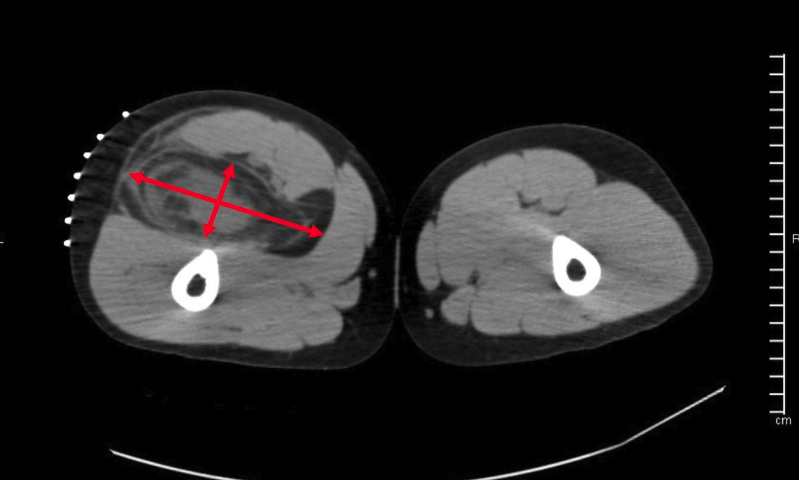

Within 2 months, the patient was able to fully ambulate. The patient was subsequently followed for 4 years without any complications until the mass was observed to grow, measuring as large as 14 x 3.8 x 2.5 cm (Figure 2).